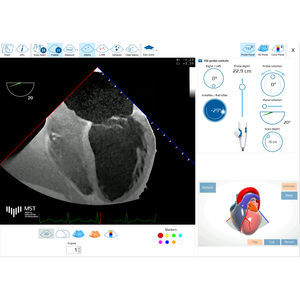

... Este es el primer sitio web con simulador online de Ecocardiografía Transesofágica dedicado a profesionales médicos. Sistema eTEEmothy se basa en MrTeemothy® y ayuda a: - comprender la anatomía tridimensional del corazón - aprender a obtener vistas ...

... La introducción más completa a la ecocardiografía transesofágica (ETE). Basado en la Web e interactivo, HeartWorks e-learn es una herramienta de aprendizaje dinámica y autodirigida para los médicos que desean consolidar sus conocimientos de TEE. Los ...

DataArt GmbH

... anatomía clave. Los usuarios manipulan fácilmente la sonda para capturar los datos correctos en la secuencia adecuada. Formación La formación interactiva paso a paso en la aplicación permite a los no especialistas aprender ...